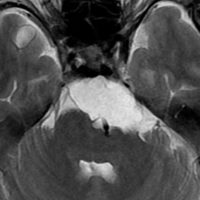

CTでは,斜台から左蝶形骨にかけて不規則な骨破壊像がみられます。

MRI T2強調画像(左)では等信号から高信号のまだらな境界が不明瞭な腫瘍が斜台から左海綿静脈洞内に浸潤しているのがみられます。T1強調ガドリニウム増強では,腫瘍がまだらに増強されています。トルコ鞍から鞍上部に伸び,視交差を侵し第3脳室底まで伸展しています。脊索腫が硬膜内に浸潤して神経組織と癒着することは珍しいことではありません。